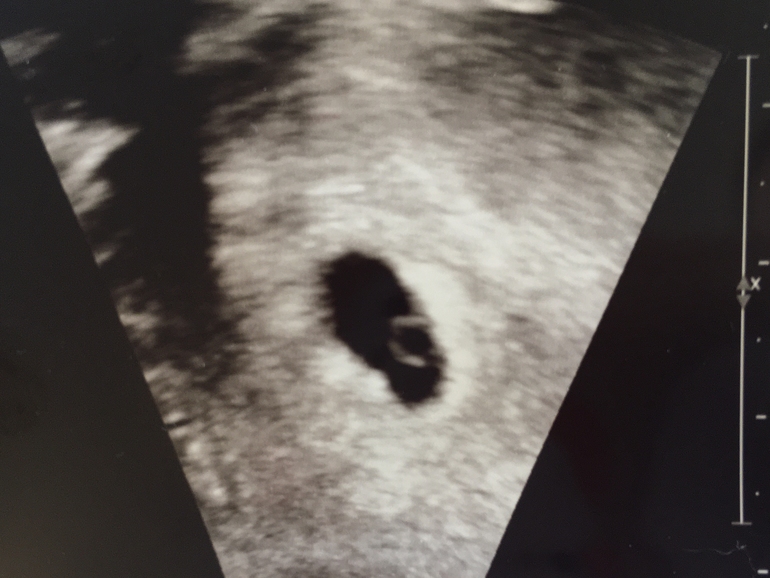

Если бы не главная новость сегодняшнего дня - УЗИ видит моего малыша, вернее ПЯ, я бы вообще бы не знаю как бы меня переклинило... А так - живу, дышу, стараюсь не переживать лишний раз. Ибо он там) Внутри: